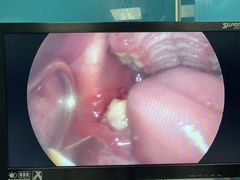

• 爱诺耐芙动物医院(万博店)

• -爱诺耐芙动物医院(万博店)

小耳朵*_1455 | 21-04-27